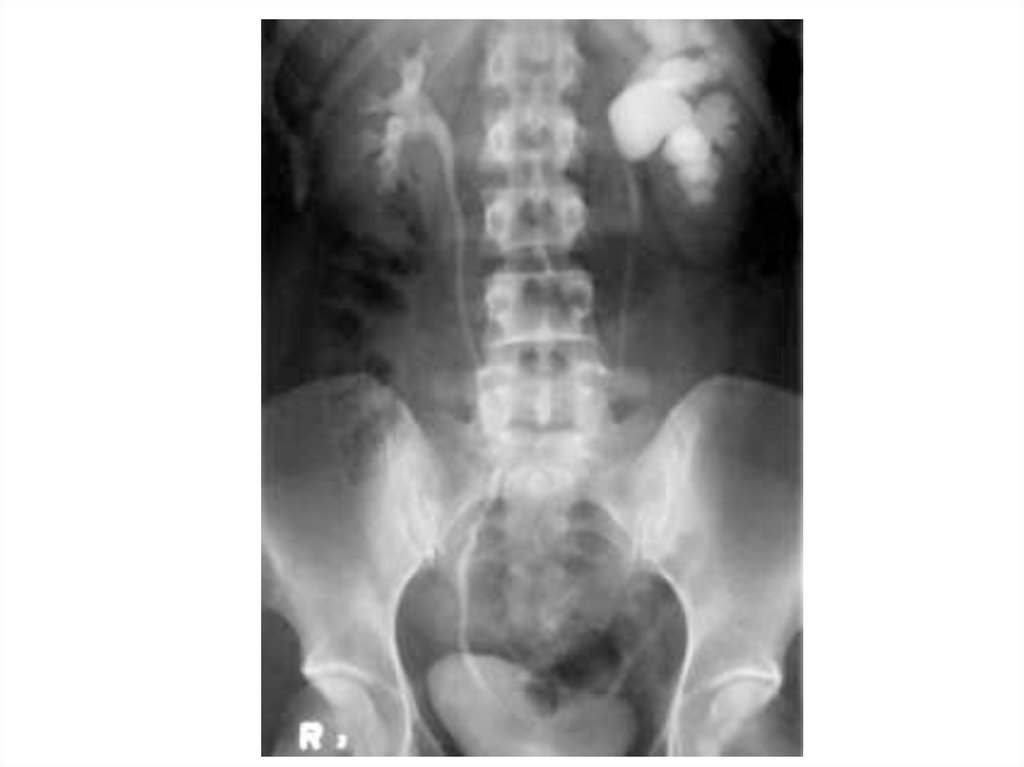

Уретерогидронефроз

19.